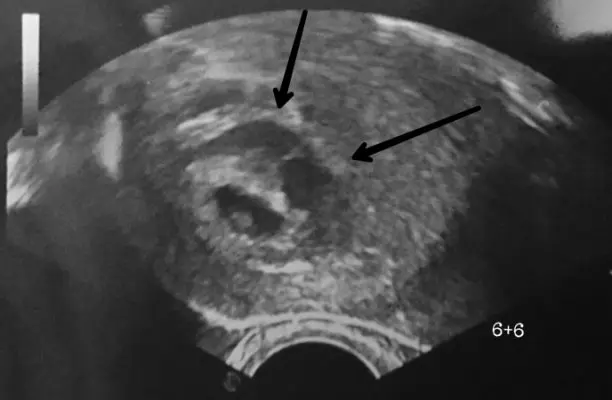

Um ein Hämatom in der Schwangerschaft zu diagnostizieren, wird der Arzt eine körperliche Untersuchung durchführen und möglicherweise weitere Tests anordnen, wie zum Beispiel:

- Ultraschall: Ein Ultraschall kann die Größe und Lage des Hämatoms zeigen.